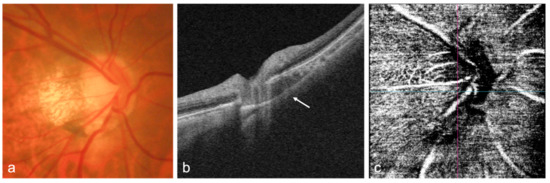

Advances in OCT Imaging in Myopia and Pathologic Myopia

Advances in imaging with optical coherence tomography (OCT) and optical coherence tomography angiography (OCTA) technology, including the development of swept source OCT/OCTA, widefield or ultra-widefield systems, have greatly improved the understanding, diagnosis, and treatment of myopia and myopia-related complications. Anterior segment OCT is [...] Read more.

Advances in imaging with optical coherence tomography (OCT) and optical coherence tomography angiography (OCTA) technology, including the development of swept source OCT/OCTA, widefield or ultra-widefield systems, have greatly improved the understanding, diagnosis, and treatment of myopia and myopia-related complications. Anterior segment OCT is useful for imaging the anterior segment of myopes, providing the basis for implantable collamer lens optimization, or detecting intraocular lens decentration in high myopic patients. OCT has enhanced imaging of vitreous properties, and measurement of choroidal thickness in myopic eyes. Widefield OCT systems have greatly improved the visualization of peripheral retinal lesions and have enabled the evaluation of wide staphyloma and ocular curvature. Based on OCT imaging, a new classification system and guidelines for the management of myopic traction maculopathy have been proposed; different dome-shaped macula morphologies have been described; and myopia-related abnormalities in the optic nerve and peripapillary region have been demonstrated. OCTA can quantitatively evaluate the retinal microvasculature and choriocapillaris, which is useful for the early detection of myopic choroidal neovascularization and the evaluation of anti-vascular endothelial growth factor therapy in these patients. In addition, the application of artificial intelligence in OCT/OCTA imaging in myopia has achieved promising results. Full article